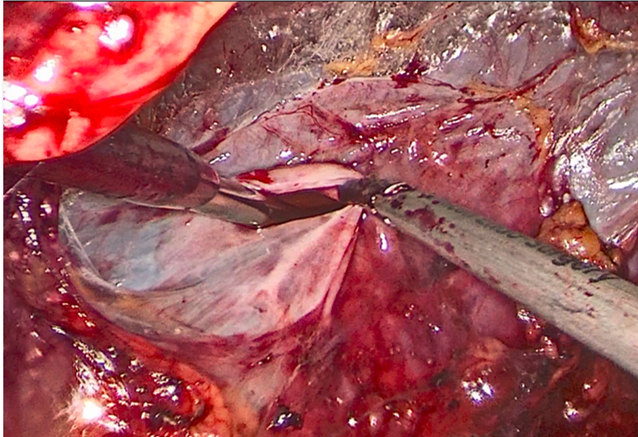

游离肾静脉,发现因长期压迫,肾实质萎缩影响,肾静脉也已萎缩

仔细游离将萎缩的动脉离断,多重夹闭防止出血

完整切除左皮囊肾和输尿管及结石,术中可见皮囊肾如同放了气的气球萎缩一般。